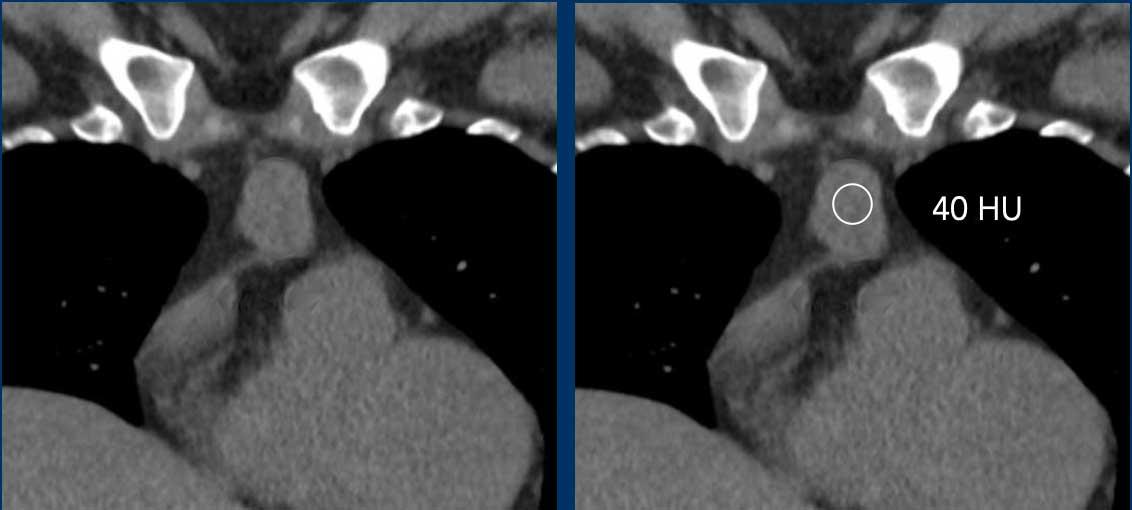

Các hình ảnh này của một phụ nữ 48 tuổi.

Trên MRI toàn thân (TWK-MRI), tình cờ phát hiện một khối ở tuyến ức.

Tiếp tục xem các hình ảnh CT…

Trên CT không tiêm thuốc cản quang (NECT), tổn thương có tỷ trọng mô mềm khoảng 40 HU.

Chẩn đoán có khả năng nhất ban đầu là u tuyến ức (thymoma).

Tổn thương đã được phẫu thuật cắt bỏ và kết quả bất ngờ cho thấy đây là một nang.

Lý giải cho hình ảnh học gây nhầm lẫn này là nang chứa dịch giàu protein, điều này giải thích cho tỷ trọng cao trên NECT.

Hình ảnh trông như ngấm thuốc tương phản trên chuỗi xung T1W có fat saturation có thể là do hiện tượng bão hòa mỡ không đồng nhất.

Tiếp tục xem hình ảnh tiếp theo…

Lưu ý hiện tượng bão hòa mỡ không đồng nhất (mũi tên).

Điều này dẫn đến hiện tượng ngấm thuốc giả (pseudo-enhancement) và chẩn đoán sai.

Chẩn đoán cuối cùng

Nang tuyến ức.